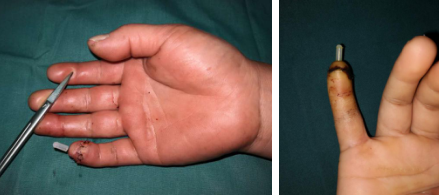

“这能接上吗?”家住徐州泉山区的马阿姨,从市区一三甲医院推荐过来,抱着试试看的心态,来到了仁慈医院手外科。这位马阿姨是被小孙子关卧室门时,不慎挤伤--指尖部的完全离断,如果是用皮瓣来修复创面,拆东墙补西墙,无疑对供区带来损伤,而且耐磨程度也不够,最好的办法就是给她接上,让它”破镜重圆”,可是这是谈何容易呀!马阿姨糖尿病、高血压多年,身体基本条件也不是太好,但是患者抱着最后一丝希望来到我院,不能让她失望而去呀,经过唐洪伟小组反复讨论,确定手术方案—清创再植!

术中吻合血管情况,血管管径仅有0.3mm

唐洪伟医生说:这个手术难度比较大,令人头疼。主要是血管太细,不容易找到,找到以后,需要非常高的显微外科技术,可能很多人一看这种情况,就直接放弃再植手术了。还有就是患者高血压、糖尿病多年,血管有不同程度的硬化,弹性差,影响术后成活,同时也面临着万一不成话,还需要二次手术等心理压力,不过看着病人,对我信任的眼神和殷切的希望,我还是决定立即行再植手术。现在患者手术成功,功能正常,手指活动非常灵活,非常满意。